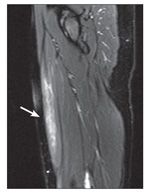

Figure 2 –

A sagittal MRI view shows a rectus femoris strain (arrow). In one study, injuries that involve more than 15% of the rectus femoris cross-sectional area resulted in a longer rehabilitation interval and strains longer than 13 cm also resulted in a prolonged recovery time.

Cross and associates24 reported that MRI may be used to estimate the size of a quadriceps strain and help predict the prognosis for acute quadriceps injuries. Injuries that involve more than 15% of the rectus femoris cross-sectional area resulted in a longer rehabilitation interval. Strains longer than 13 cm also resulted in a prolonged recovery time (Figure 2).